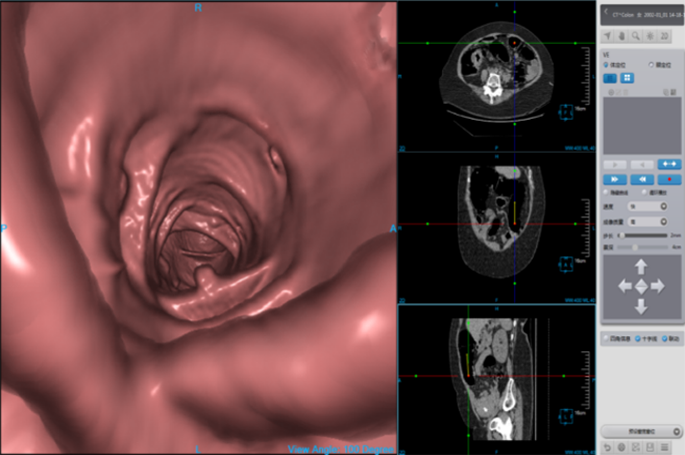

Cardiac Viewer Images

View heart images of each phase, execute three-dimensional reconstruction and heart extracted for CT heart images, and then view patient heart by more intuitive way, diagnosis various cardiovascular diseases.

• Different phases data comparison

• 4D play

• Oblique MPR display